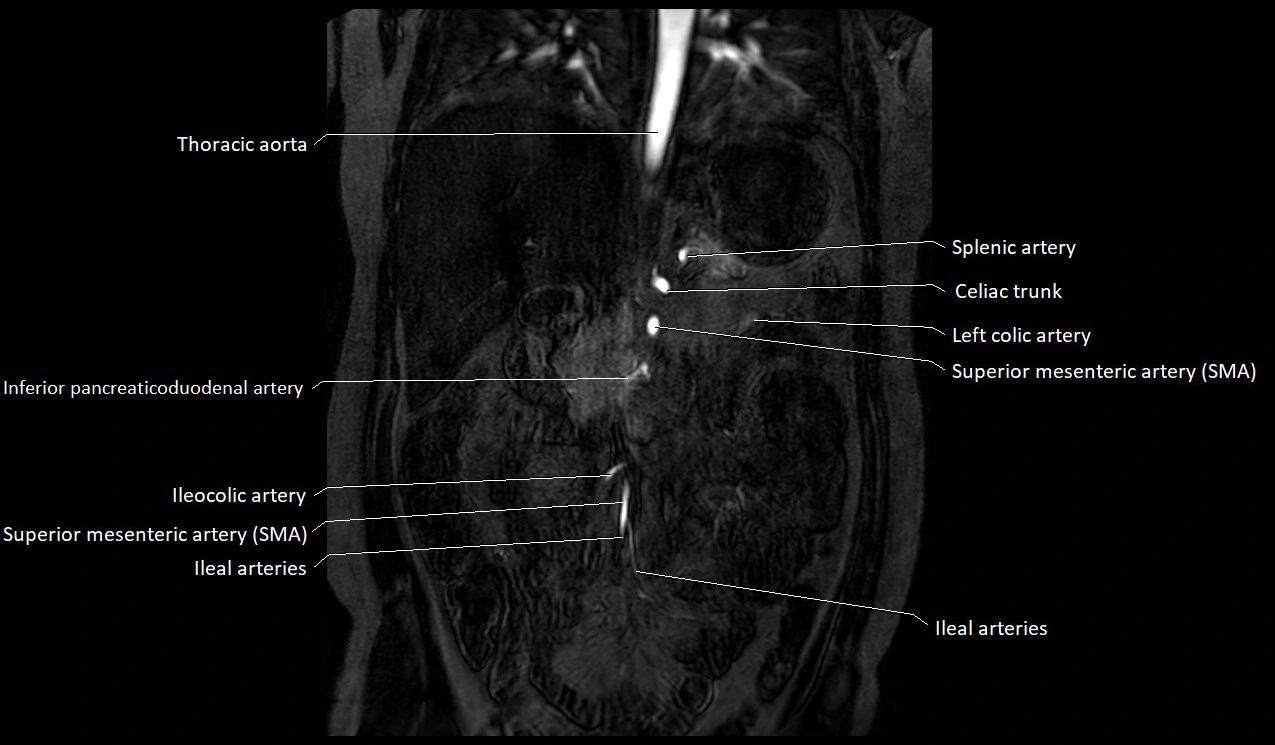

MRI Appearance

T1-weighted images:

Artery appears as a small linear hypointense flow void coursing over the superior pubic ramus

Seen within bright perivascular fat of pelvis

T2-weighted images:

Artery lumen is a signal void

In thrombosed or diseased variants, lumen may appear hyperintense relative to surrounding fat

STIR:

Fat suppression makes the artery more visible within pelvic fat

Helps identify perivascular edema, hematoma, or inflammatory changes

T1 Post-Gadolinium (with fat suppression):

Artery enhances brightly and homogeneously

Useful for tracing the course, anastomoses, and presence of corona mortis

Highlights arterial wall thickening or tumor encasement if present

MRA Pelvis with Gadolinium:

Clearly delineates the origin, course, and anastomoses of the accessory obturator artery

Identifies connection with inferior epigastric artery, external iliac artery, or obturator artery

Excellent for detecting vascular variants prior to surgery

Useful in mapping pelvic vasculature in trauma, tumor embolization, or preoperative planning